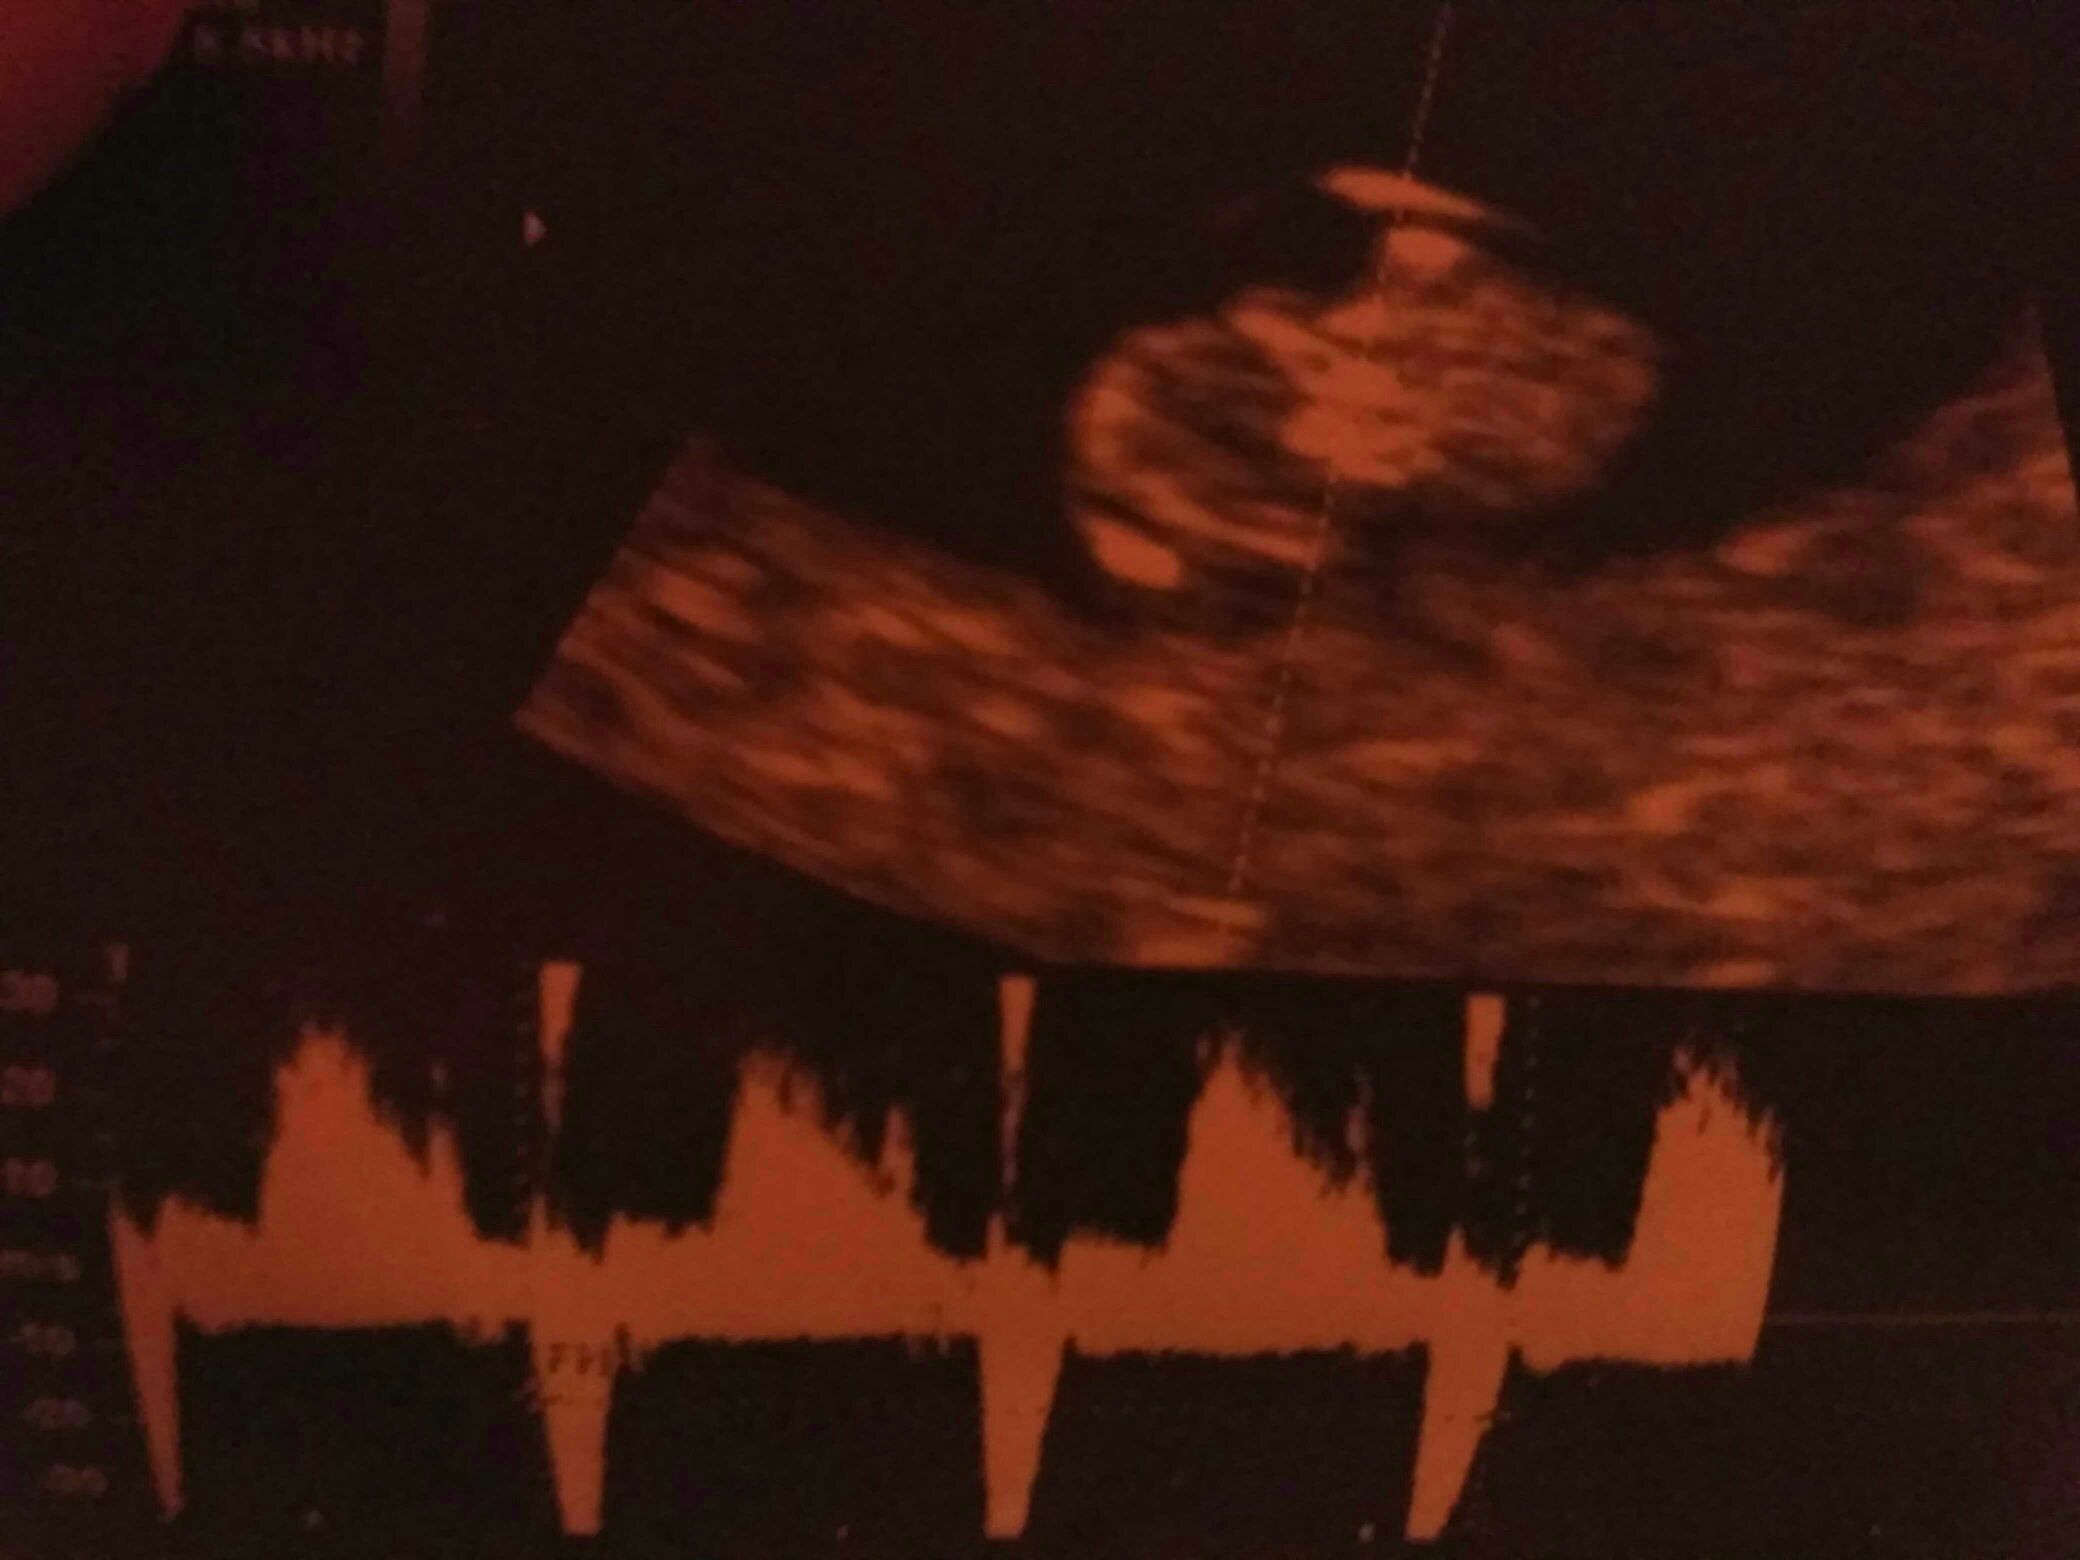

Ja mam takie zdjęcia i kompletnie nie wiem co na nich mam widzieć

To okrągłe to chyba pęcherzyk ?

Miałam takiego stresa , że serio nic nie wiem